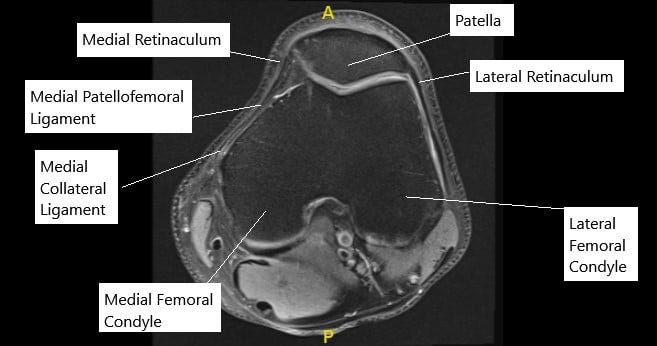

MPFL The Little Ligament That Could ProActive Physical Therapy online, Medial Patello Femoral Ligament MPFL Reconstruction online, Patellofemoral Ligament Reconstruction Knee Surgeon South online, Arthroscopic reconstruction of the medial patellofemoral ligament online, Medial Patellofemoral Ligament Tears Minneapolis MN Sports online, Medial Patellofemoral Ligament Reconstruction Techniques online, Patellofemoral Instability in the Skeletally Immature Patient A online, Medial Patellofemoral Ligament Surgery In Tamilnadu online, Physical Therapy for Medial Patellofemoral Ligament Injury online, PDF Management of medial patellofemoral ligament injury A case online, Medial Patellofemoral Ligament Injury MPFL Specialist Sugar online, Arthroscopy Journal on X online, The Medial Patellofemoral Ligament of the Knee by Nabil Ebraheim online, Figure 4 from The medial patellofemoral ligament Review of the online, Medial patellofemoral ligament reconstruction technique online, Graphic illustration of double bundle medial patellofemoral online, MPFL reconstruction animation online, What is the difference between MCL and MPFL ligaments and does online, Dynamic Anatomical Reconstruction of Medial Patellofemoral online, MPFL Injury Medial Patellofemoral Ligament MPFL Tear online, Your Patellofemoral Ligaments and Cartilage Spring Loaded Technology online, MPFL Reconstruction Hertfordshire Patellar Instability online, Medial Patellofemoral Ligament Reconstruction Complete Orthopedics online, Medium to long term outcomes of medial patellofemoral ligament online, Figure Diagram of the patellofemoral ligaments. Contributed by online, Medial Patellofemoral Ligament Tear Moreno Valley CA MPFL online, Medial Patellofemoral Ligament Of The Knee Anatomy Everything You Need To Know Dr. Nabil Ebraheim online, The Medial Patellofemoral Ligament MPFL The Basics BSM Foundation online, Medial Patellofemoral Ligament MPFL Reconstruction Knee online, Medial Patellofemoral Ligament MPFL Gorav Datta online, Medial Patellofemoral Ligament Reconstruction Sydney Knee online, Medial Patellofemoral Ligament Injury Recovery Capital Area PT online, Medial Patellofemoral Ligament MPFL Reconstruction HSS online, Medial Patellofemoral Ligament Injury MPFL Tear MPFL online, Medial Patellofemoral Ligament MPFL Physiopedia online, Product Info: Medial patellofemoral ligament online.